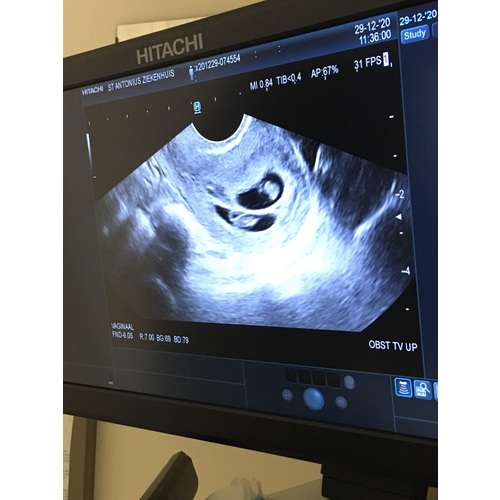

Wij hebben vandaag een echo gehad met 10+3 weken. En toch een verrassing: het is een eeneiige tweeling. Ze waren gelukkig even groot en lekker beweegelijk. Vanaf nu elke twee weken een echo.